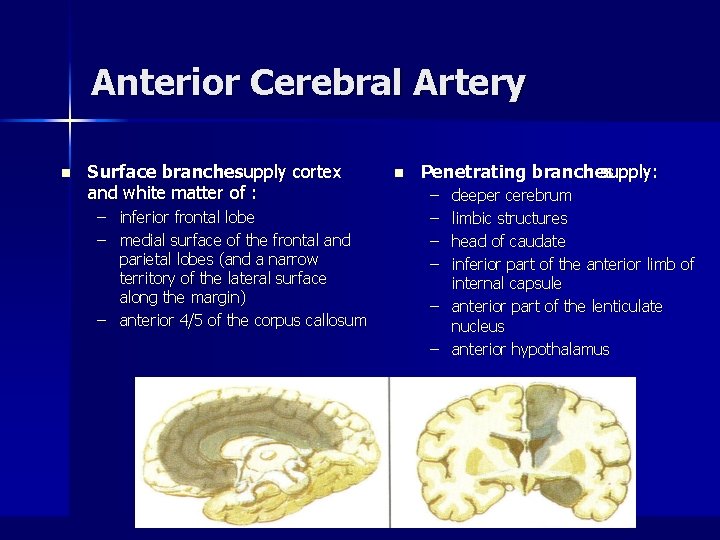

Anterior Cerebral Artery n Surface branchessupply cortex and white matter of : – inferior frontal lobe – medial surface of the frontal and parietal lobes (and a narrow territory of the lateral surface along the margin) – anterior 4/5 of the corpus callosum n Penetrating branches supply: – – deeper cerebrum limbic structures head of caudate inferior part of the anterior limb of internal capsule – anterior part of the lenticulate nucleus – anterior hypothalamus